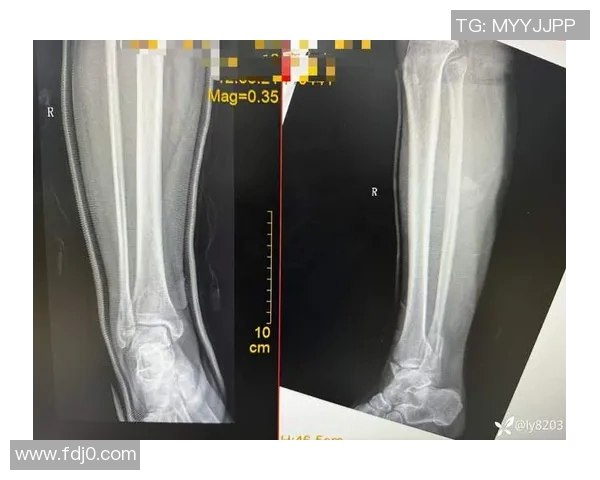

踝关节骨折在足球运动中并不少见,这一伤害往往是由于剧烈碰撞或者不当落地造成的。由于足球比赛中快速变向、急停以及身体对抗频繁,球员们很容易因外力作用导致脚踝部位受伤。而对于职业球员来说,一次严重的踝关节骨折可能意味着整个赛季甚至更长时间无法参赛。

此外,踝关节本身结构复杂,包括多条韧带和多个骨骼,在遭受重创时,其损伤程度也会有所不同。有些球员可能只需经过短暂休养便可复出,但另一些人则可能因为韧带撕裂等情况需要手术治疗。这种情况下,不仅影响了他们的竞技状态,也给心理上带来了巨大的压力。

随着科技的发展,现代医学为运动损伤治疗提供了更多创新的方法和技术,这无疑为众多遭遇踝关节骨折的足球明星打开了新的希望之窗。不少医院已引入先进设备,通过精准影像学检查确定损伤程度,从而制定个性化治疗方案。例如,有些运用干细胞技术加速愈合过程,使得患者能够更快恢复功能。